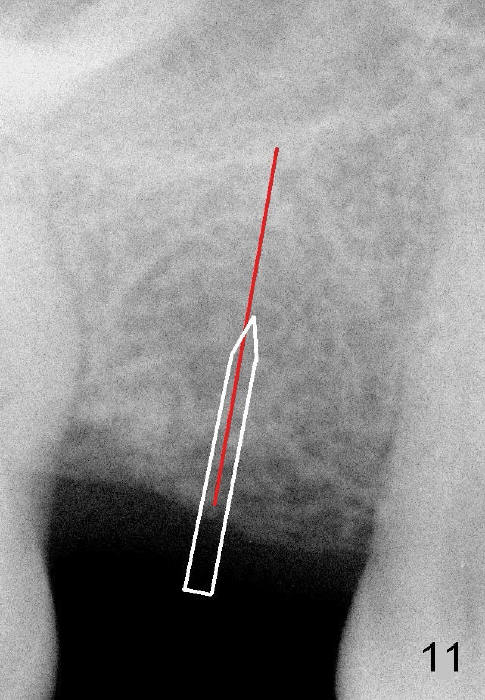

Another drawback of the implant placement is that the trajectory is off and distal (Fig.3-6), probably due to the low bone density in the distal aspect of the socket prior to extraction (Fig.7 CT sagittal section; MB: mesiobuccal root). The pilot drill must inadvertently have drifted distally and to the less dense bone (Fig.8). If it had been found, it could have been corrected early (Fig.9 red arrow). The trajectory could have been corrected immediately after the 2.6 mm expander (Fig.10). Ideally the pilot drill (Fig.11arrow) should be placed slightly mesial to the presumably mid edentulous line (red line) and only half of the length. If the trajectory is right, continue osteotomy (Fig.12). If not, correct it immediately.